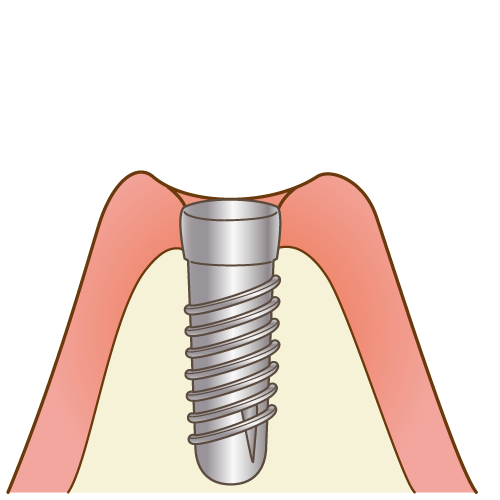

4一次手術

インプラントは、人工歯根、アバットメント、人工歯(セラミックの被せ物)の3パーツで構成されます。

一次手術では、顎の骨に人工歯根を埋め込みます。

一次手術では、顎の骨に人工歯根を埋め込みます。